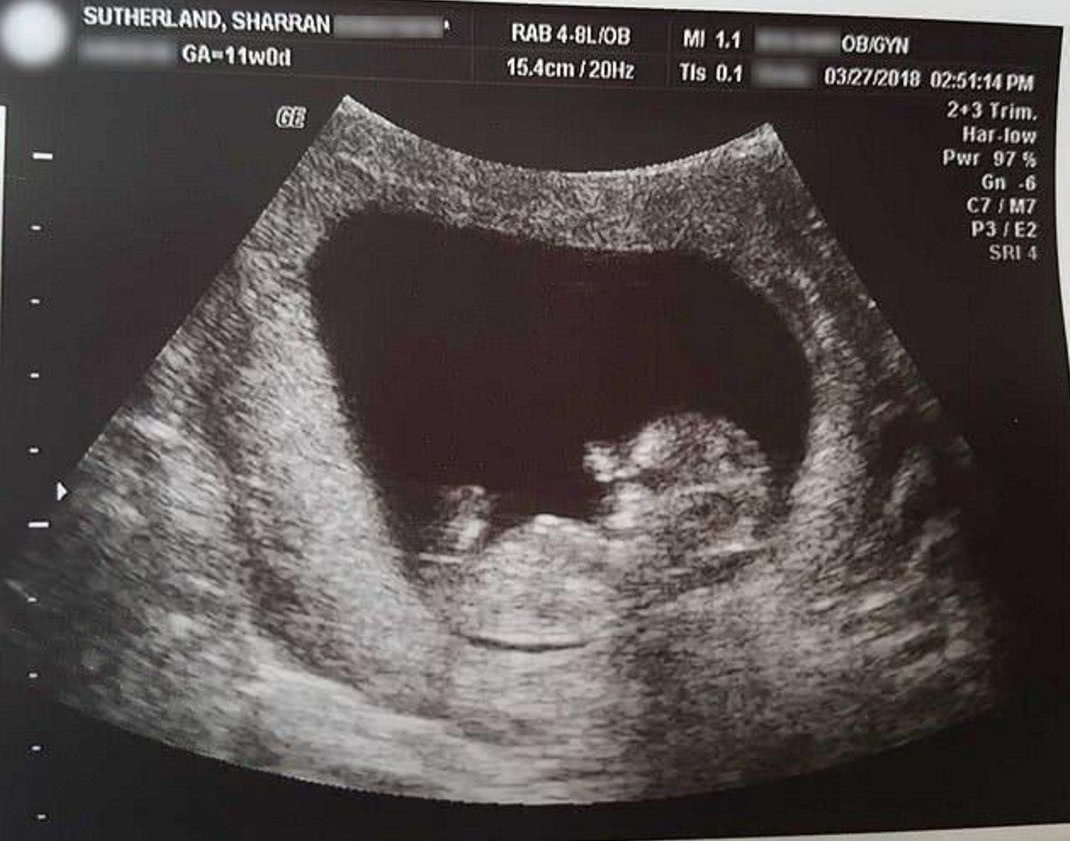

导读:孩子在母亲腹中死亡,母亲不希望孩子变医疗垃圾,带回家种花盆里每个做母亲得到都非常希望自己的孩子可以健康的出生,平平安安的长大,现在有很多的未成年人,因为一时的冲动不能对自己的行为负责任,所以导致了要去医院流产,他们意识不到那是一个生命。在美国的密苏里州的莎兰·萨瑟兰已经有40岁了,她和她35岁的丈夫迈克尔一共有11个孩子,但是在她40岁的怀孕的时候还非常的高兴,他们一家人都非常期待这个孩子的到来,但是或许是她年纪大了,怀孕14周的时候孩子在她的肚子里没有了心跳。

当时医生就建议她做流产手术,但是做流产手术的话就意味着孩子的身体就会被分成两半,而她不想要自己的孩子变成一个医疗垃圾,所以选择了自然分娩,当孩子出来的时候他的手和脚都已经成型了,他们还给这个孩子取名叫做米兰。这个宝宝是一个男孩,只有10厘米长,22.7克重,但是他的手和脚都已经成型了甚至连指甲都已经长出来了,唯一不同的是这个孩子已经失去了血色的身躯,莎兰把孩子放在自己的手里,他的一切都很完美,但很可惜的时候不能将他带来这个世间。